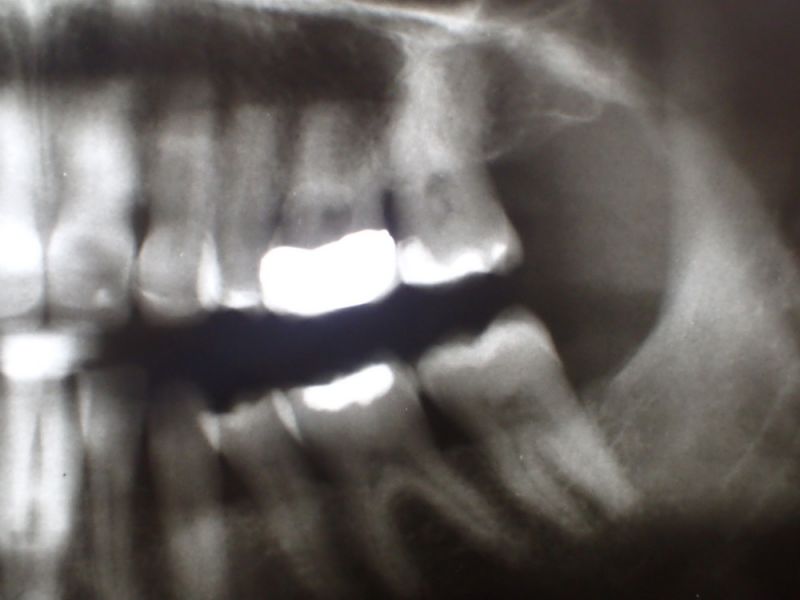

In diesem Zusammenhang wurde heute noch ein Übersichtsröntgenbild erstellt, dass einen ganz typischen, aber häufig nicht bekannten Befund mit sich bringt.

Obwohl die Patientin erkennbar eine gute Mundhygiene beteibt, zeigt sich im gesamten Oberkiefer und hier vor allem im Bereich der Backenzähne ein ausgeprägte und altersuntypisch weit voran geschrittener Knochenabbau.

Das Typische an diesen Zuständen besteht darin, dass der Knochen im Unterkiefer weitgehend normal erscheint, was bene gerade dafür spricht, dass es sich um kein mundhygienebedingtes Problem des Kieferknochenabbaus handelt.

Sollte über die Funktionsdiagnostik hinaus in diesem Fall eine Funktionstherapie zustande kommen, wäre deren Ziel nicht nur die Beseitigung/Linderung der bekannten funktoinellen Beschwerden, sondern darüber hinaus der Stopp des anhaltenden alveolären Knochenabbaus.